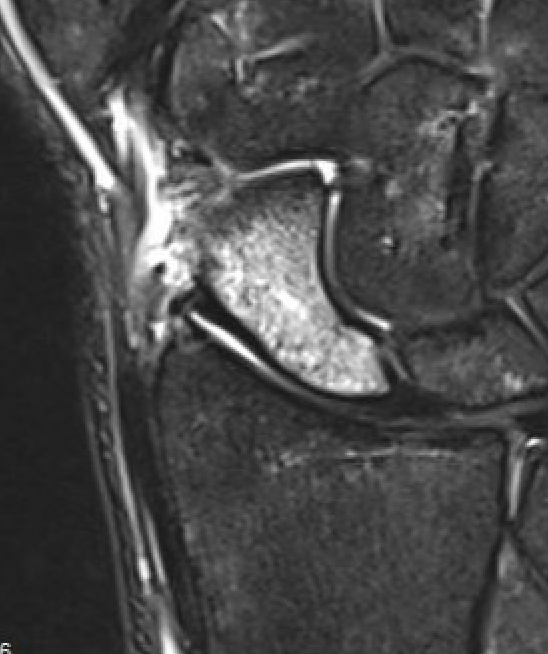

MRI

Indications

- occult fractures

- diagnosis of AVN

Occult scaphoid fracture on MRI

- 67 patients with normal xray and suspected scaphoid fracture

- 10% had scaphoid fracture on MRI

Dean et al Bone Joint Open 2021

- 258 patients with normal xray and suspected scaphoid fracture

- 13% had scaphoid fracture on MRI, 6% scaphoid contusion